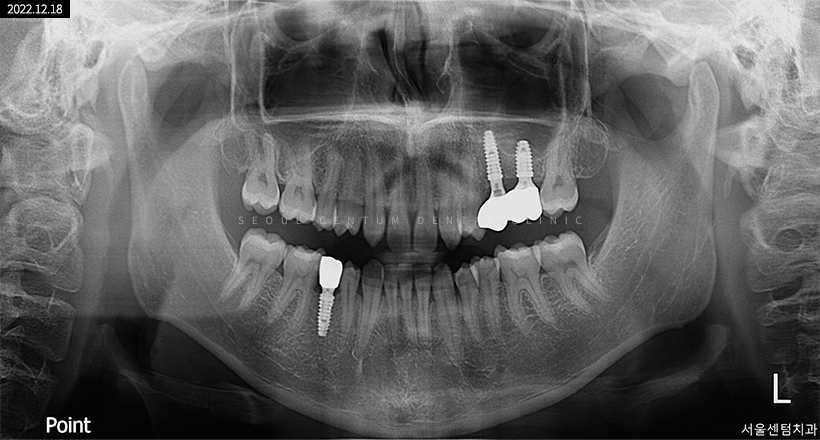

실제로 저희 치과에 내원해 주신 한 환자분의 파노라마 엑스레이 사진입니다.

임플란트2차수술과정은 먼저 잇몸을 개방하고 픽스처를 체결한 위치에 어버트먼트를 연결해 보철물을 장착할 수 있도록 다시 봉합시키고 치아본을 뜹니다. 그리고 약 2주 뒤에 지르코니아 같은 보철물을 장착하는 것이 되겠습니다. 임플란트2차수술과정은 1차에 비해 난도가 낮기 때문에 수술 시간이 10~20분으로 짧고 통증이나 출혈도 덜합니다.

임플란트 1차 / 2차 수술 기간

임플란트를 1차만 하면 23개월 정도가 소요되는 편이지만 2차 임플란트까지 진행하는 경우에는 1차 수술 후 골융합이 충분히 이뤄질 수 있는 기간(약 23개월)이 경과 후 진행합니다. 그래서 1차와 2차 임플란트 수술을 해야 한다면 총 3~6개월 정도가 소요되며 뼈이식을 많이 진행하거나 골융합 속도가 더딘 등의 이유로 기간이 더 길어질 수도 있습니다.